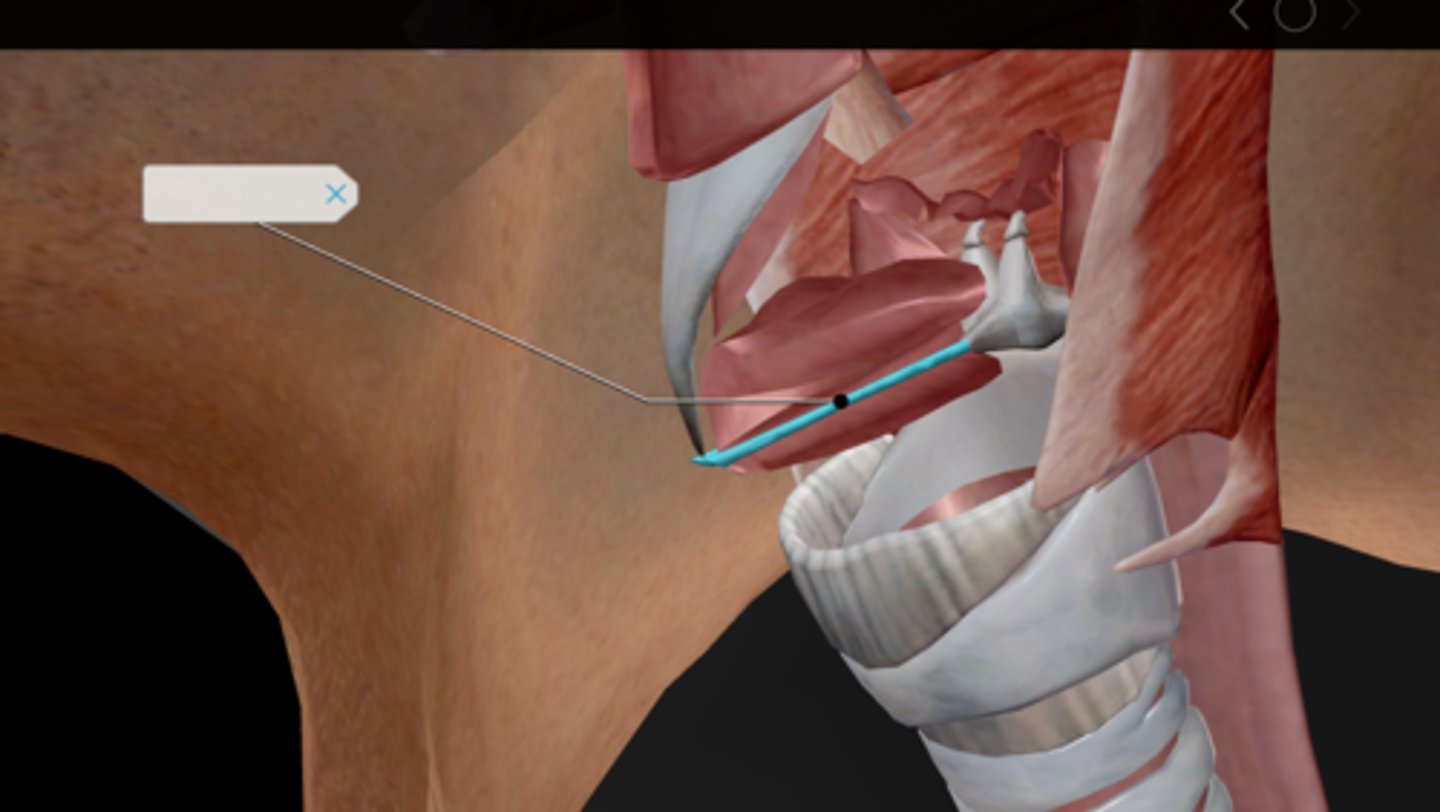

Larynx

Epiglottis

Thyroid cartilage

Cricoid cartilage

Vocal ligament

Vocal folds

Vestibular folds

Trachea

Tracheal cartilaginous rings